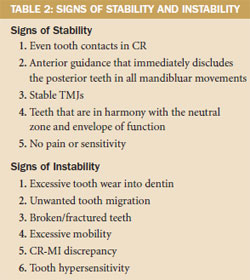

The complete examination is supplemented with vital diagnostics including full-mouth and panorex radiographs, CT/MRI (if appropriate), photographs, study models, and facebow and CR bite records. The clinician should search for stability and instability during the examination (Table 2). The TMJs are considered stable for occlusal therapy if any noted disorders are extracapsular or involve only lateral pole disk displacement (Piper TMJ Class IIIB or lower). If medial pole derangement of the articular disk is diagnosed (Piper Class IVA or higher), then long-term splint therapy is considered appropriate before changing the occlusion. With a complete examination, most temporomandibular disorders can be stabilized; failure to address this issue prior to treatment may have devastating effects on newly placed porcelain restorations.4-6

The patient was concerned that new bridges could similarly fail and was averse to removable prosthetics. He wanted to reduce risk, increase function, and improve his esthetics while having individual teeth. Initial analysis revealed several signs of instability (Table 2): CR-MI discrepancy and posterior working and balancing interferences during protrusive and lateral movements of the mandible were recognized. These were thought to be largely responsible for the noted damage (Figure 4, 5, 6, 7, 8). Records were prescribed to accurately diagnose the condition and develop a treatment blueprint.